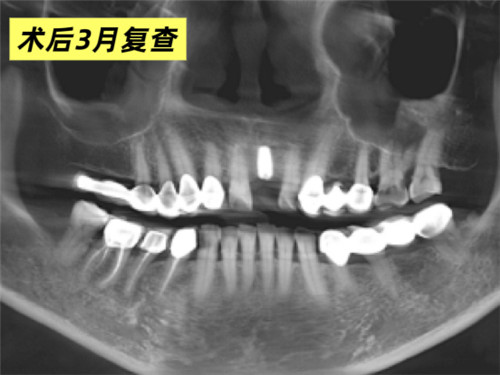

口腔科主任牛躍、副主任醫(yī)師鮑磊接診后,為其完善術(shù)前CBCT(口腔頜面錐形束CT)檢查,細(xì)致評(píng)估口腔條件,發(fā)現(xiàn)患者牙槽骨吸收嚴(yán)重,骨厚度僅4mm,術(shù)中需要植入人工骨粉。在征得患者同意后,科室團(tuán)隊(duì)精準(zhǔn)操作,術(shù)中植入骨粉并覆蓋骨膜,僅用30分鐘便成功完成手術(shù)。3個(gè)月后復(fù)查CBCT,植體與周圍骨質(zhì)結(jié)合良好,科室團(tuán)隊(duì)行牙冠修復(fù)后,患者對(duì)最終效果非常滿意,重新綻放自信笑容。